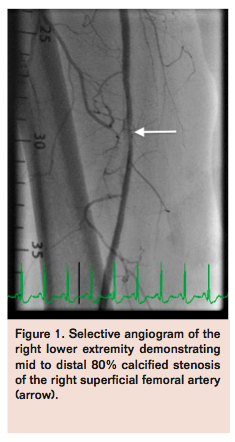

Access was obtained in the left common femoral artery (CFA) and a 7 Fr Pinnacle Destination sheath (Terumo) was positioned across the aortic bifurcation in the right CFA. Selective angiogram of the right lower extremity confirmed mid to distal 80% calcified stenosis of the right SFA (Figure 1), mild popliteal artery disease, and 2-vessel run-off into the right foot. A Grand Slam Wire (Abbott Vascular) was advanced across the right SFA lesion into the distal peroneal artery after anticoagulation with intravenous heparin. Intravascular ultrasound (IVUS) imaging (Volcano) was performed to determine the burden and character of the plaque, which confirmed a severe calcific and eccentric stenosis in the mid SFA (Figure 2). Rotational atherectomy with aspiration thrombectomy was performed using a Jetstream 2.1/3.0 atherectomy catheter (Bayer HealthCare) with four passes across the lesion, two with blades down and two with blades up (Figure 3). Follow-up angiography displayed improved flow but with a non-flow-limiting dissection within the treated segment of the right SFA (Figure 4). Repeat IVUS imaging confirmed an intimal flap consistent with post-atherectomy dissection (Figure 5). Nitinol-constrained balloon angioplasty was performed using a 5 mm x 80 mm over-the-wire Chocolate PTA balloon catheter (TriReme Medical) with a prolonged expansion over 2 minutes (Figure 6). Final angiogram demonstrated excellent angiographic result with brisk flow through the treated segment (Figure 7) and preserved run-off into the foot. Final IVUS imaging confirmed no residual dissection flap and improved luminal gain (Figure 8).